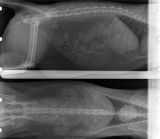

Radio abdominale

Mégaoesophage

Fécalome